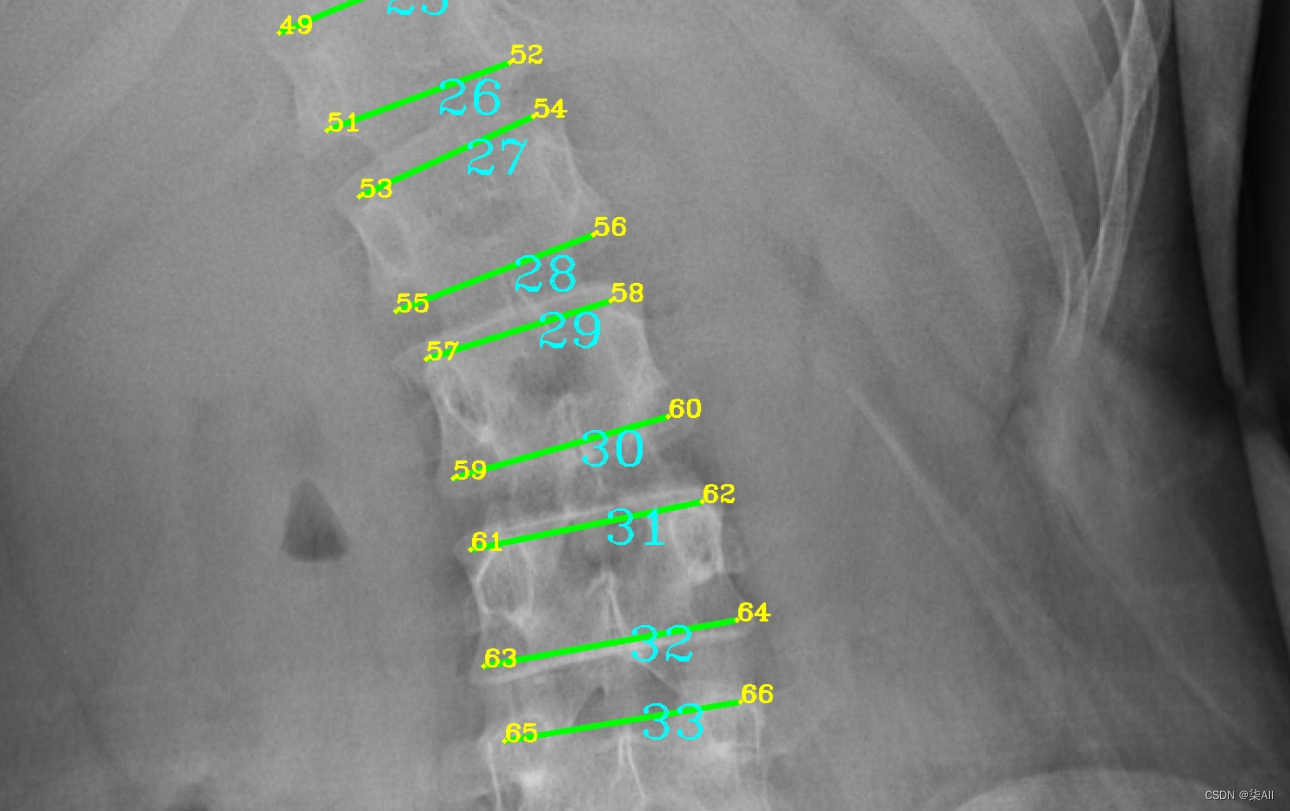

- (6)你看这种58这种点,咱们可以往外标一点,或者把60缩一些

(6)你看这种58这种点,咱们可以往外标一点,或者把60缩一些